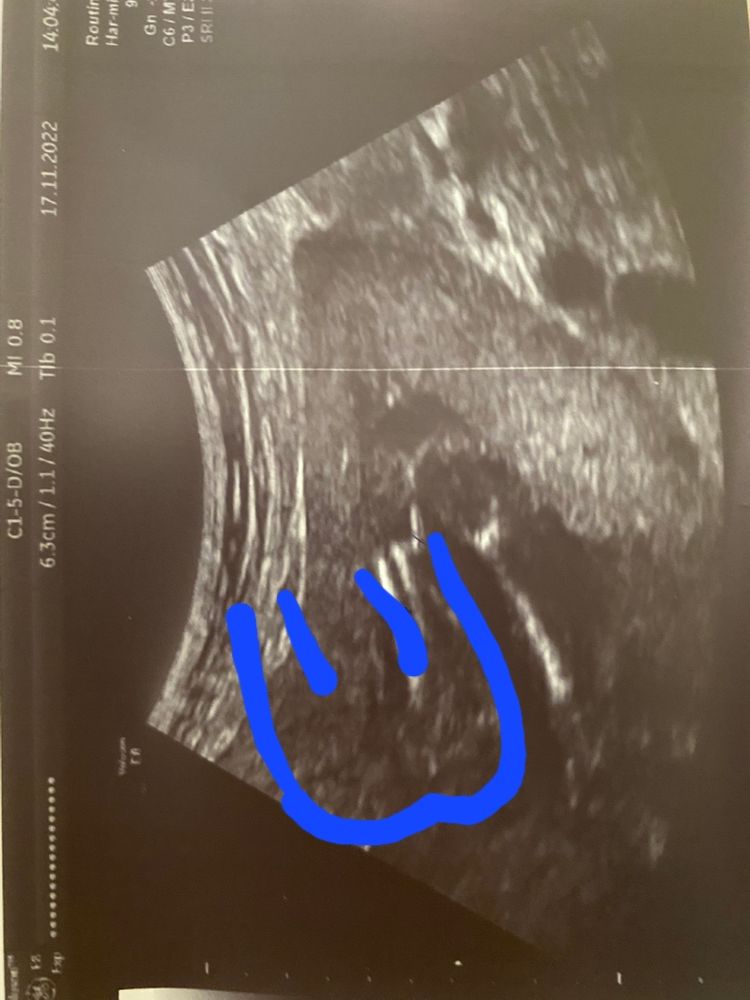

Сегодня ходила на узи по определению пола, нам 18 неделек)

может кто-нибудь сможет предположить или точно сказать наш пол, врач дал 70%

Так на снимке только одна часть попки и ножка..Второй нету и соотв-но что между ног тоже не видать на снимке🙈

МамаИрВаЛе, да уж) а Врач сказал, что это попа😂

Зачем нам тогда снимок одной ноги?) на что они рассчитывали? То что мы все равно не разберёмся?🥹🥹🥹

я вижу иную картину.Только часть.Где ручкой отмечено это кость и попы там быть не может🙈

Если смотреть-как вы отметили(Чисто логически ),как нога может у попы уменьшатся в объеме?самая толстая часть ноги у попы😁

Юлия, это видео стороны попки)

справа налево попка и ноги, там где нарисовано ручкой половой орган 🥹